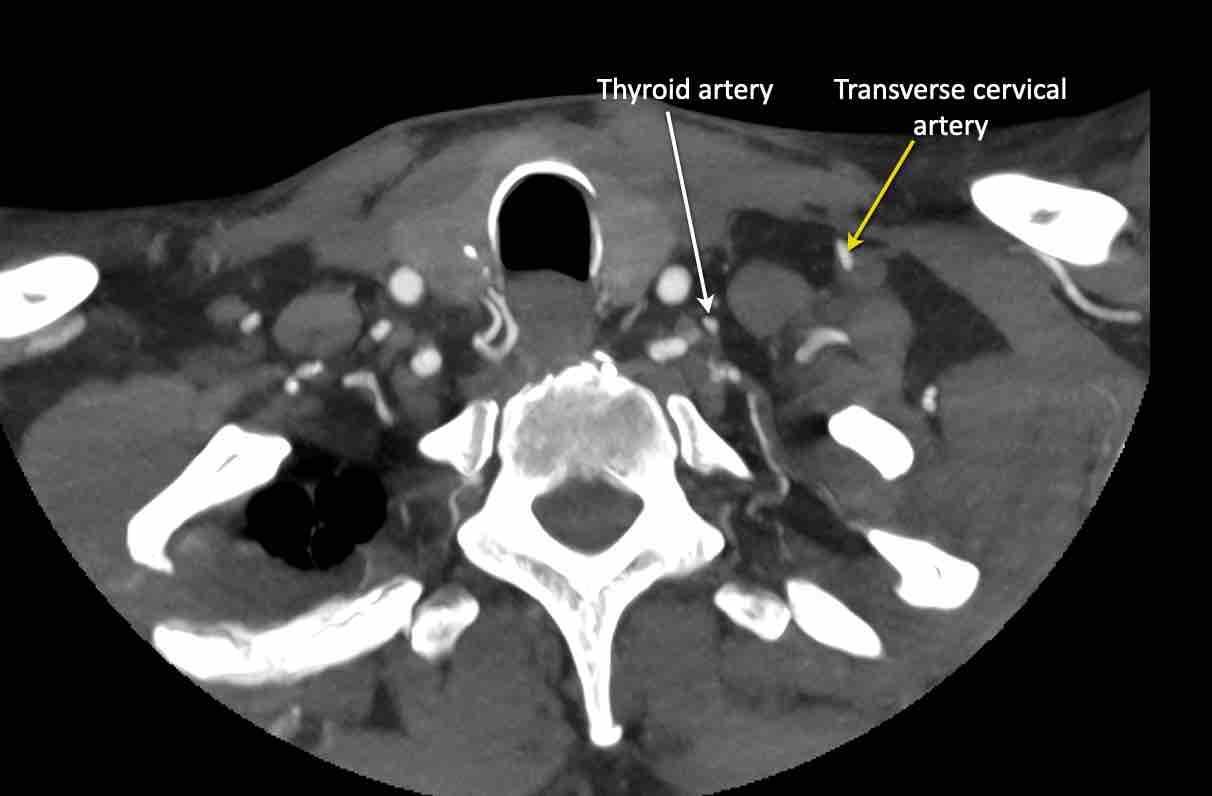

Động mạch cổ ngang

Cuộn qua các hình ảnh để xem giải phẫu của động mạch cổ ngang.